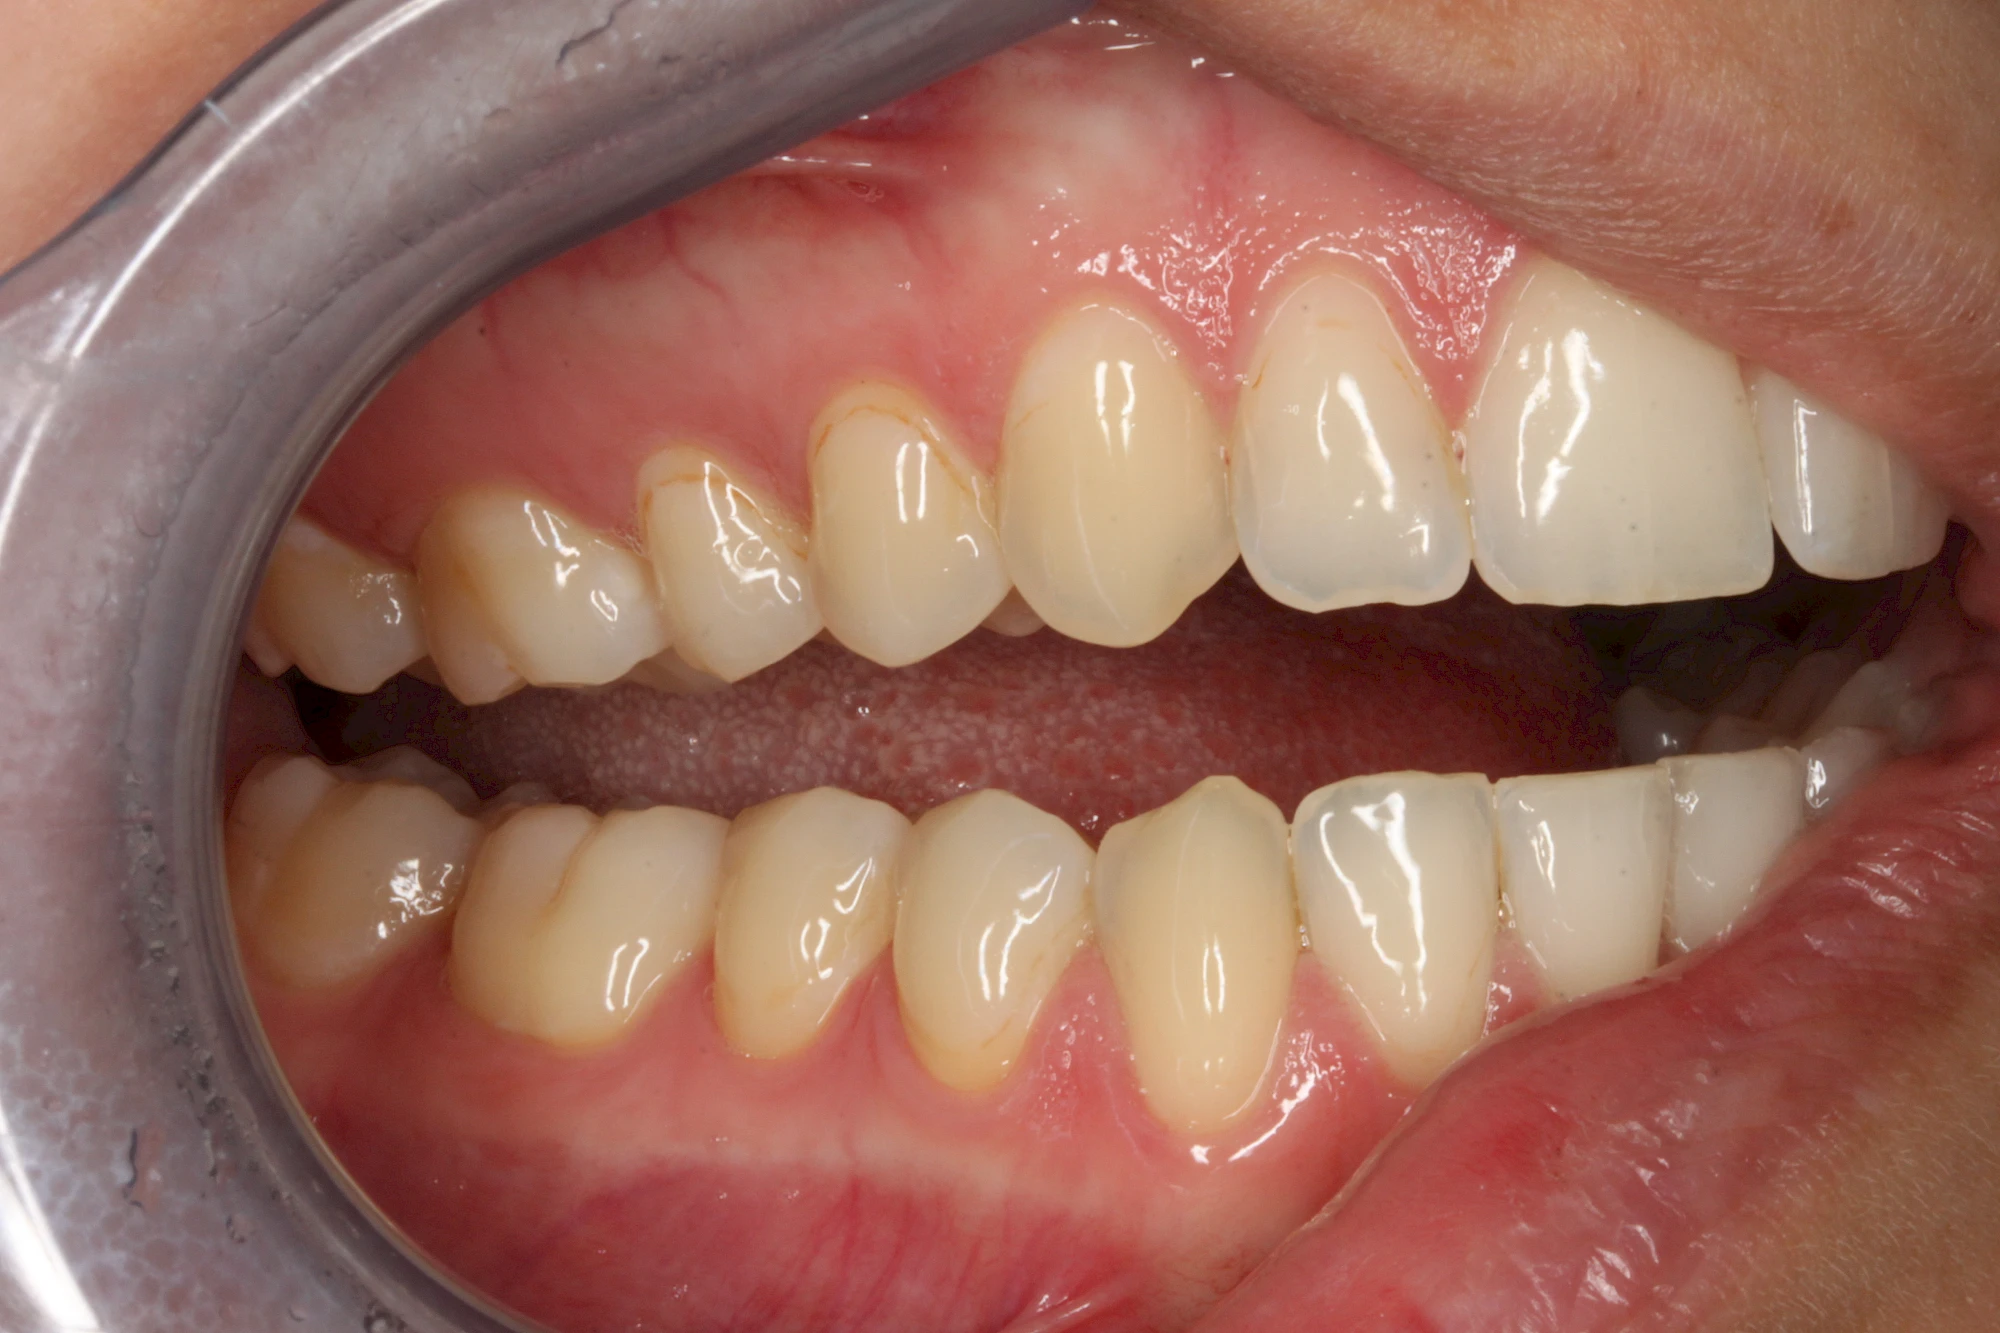

Manche Medikamente wie zum Beispiel das Antibiotikum Tetrazyklin kann bei Einnahme im Zeitfenster der Zahnentwicklung auch irreversibel in die Zahnsubstanz. eingelagert werden. Tetrazyklin verfärbt die jeweils betroffenen Zähne bläulich und sollte deshalb während der Schwangerschaft und bei Kindern nicht verordnet werden.

Daneben gibt es noch seltene genetisch bedingte Schmelz- bzw. Dentinbildungsstörungen (Amelogenesis imperfecta, Dentinogenesis imperfecta), die neben Verfärbungen vor allem auch durch Veränderungen der Oberflächenstrukturen auffallen. In diesen Fällen ist eine engmaschige Betreuung durch den Zahnarzt wichtig.